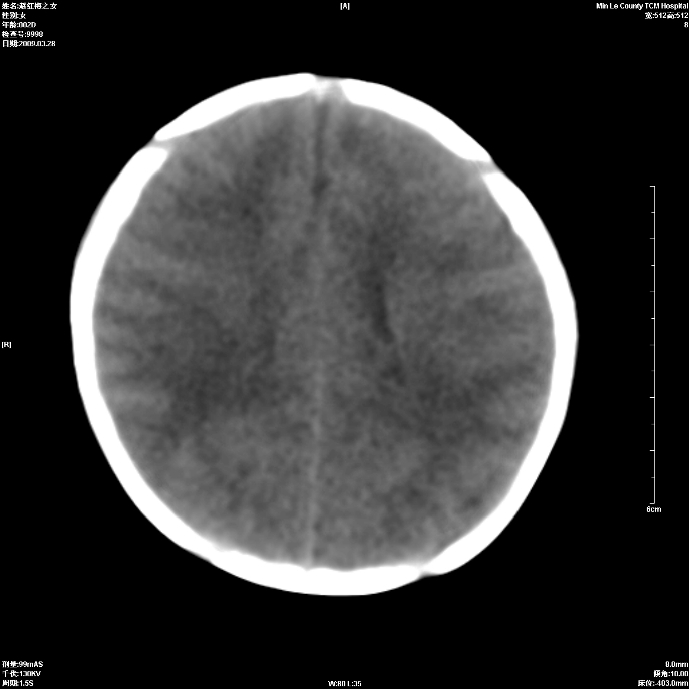

标题: PED1815:患儿出生两天,哭闹不安,囟门饱满 [打印本页]

标题: PED1815:患儿出生两天,哭闹不安,囟门饱满

支持考虑新生儿缺血缺氧性脑病伴蛛网膜下腔出血,请结合临床,建议随访复查

支持脑缺氧缺血.蛛网膜下腔少量出血.

考虑新生儿缺血缺氧性脑病伴蛛网膜下腔出血

缺氧缺血性脑病